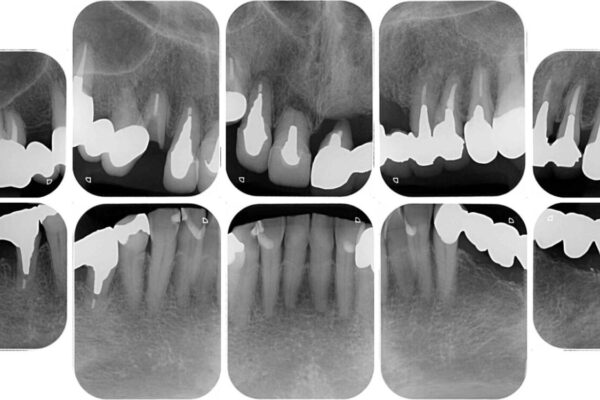

上顎犬歯や下顎大臼歯は、必要なところはインプラントを埋入することとしました。

クラウンが不適合であったり、根管治療の必要なほどの痛みのある歯であったり、見た目の気になる前歯などをオールセラミッククラウンに補綴治療を行うこととしました。

治療前